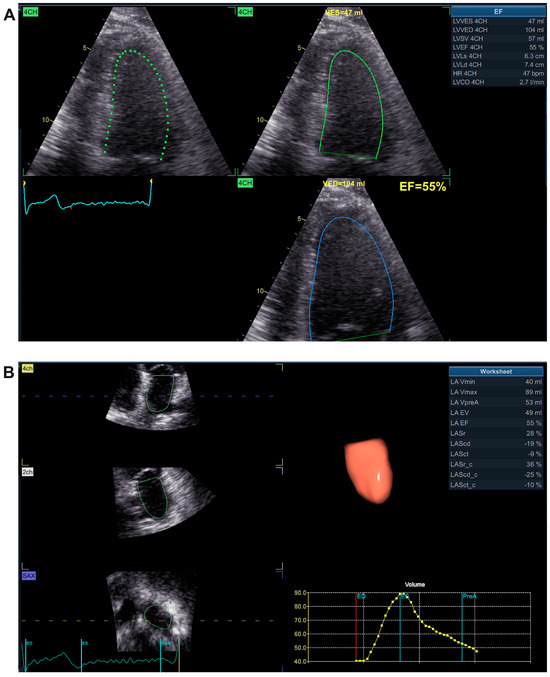

| Echo parameters | LVEF (%) | 52.96 ± 4.306 | 54.27 ± 2.796 | 0.3309 |